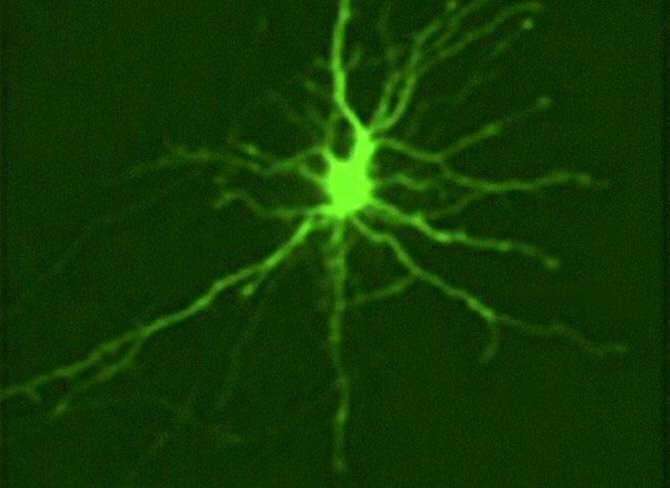

En la enfermedad de Huntington (una de las identificadas popularmente como Baile de San Vito o Mal de San Vito) y en muchos otros trastornos neurodegenerativos, las proteínas que están plegadas incorrectamente (y tienen por ende formas anormales) se acumulan dentro de las neuronas y también a su alrededor, y se cree que dañan y matan a las células cerebrales circundantes. Normalmente, las células perciben la presencia de proteínas mal plegadas y las eliminan antes de que puedan producir cualquier tipo de daño. Esta función protectora se basa en un proceso llamado proteostasis, que es utilizado por la célula para controlar los niveles y la calidad de las proteínas.![[Img #15090]](upload/img/periodico/img_15090.jpg)

En este estudio, Andrey S. Tsvetkov y sus colaboradores de la Universidad de California en San Francisco y la Universidad Duke en Durham, Carolina del Norte, ambas instituciones en Estados Unidos, mostraron que las diferencias en la velocidad de la proteostasis pueden ser la clave para entender por qué ciertas células nerviosas mueren durante la enfermedad de Huntington, una dolencia genética cerebral que produce movimientos descontrolados y otros problemas.